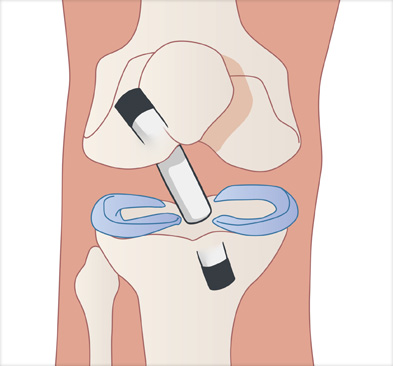

십자인대 재건술은 손상된 인대를 자가건이나 타가건을 활용해 원래의 인대의 위치에 재건하여 무릎의 기능을 회복시킵니다.

이식할 인대 삽입

이식한 인대 고정